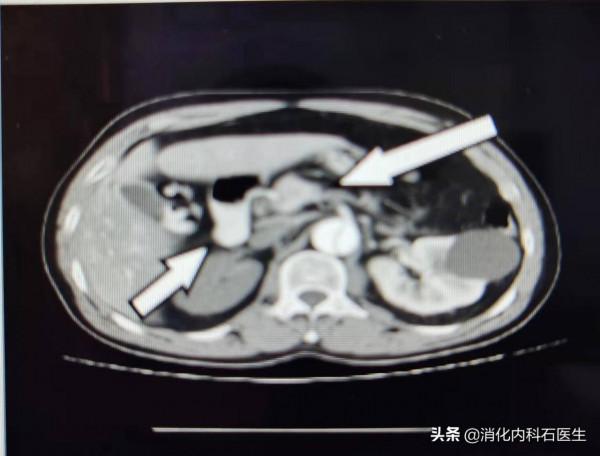

腹部強化CT馬上安排,結果一出,主任坐不住了。

腹部強化CT顯示:(1)主動脈夾層。(2) 右腎供血不足,考慮右腎梗死

考慮腹主動脈夾層並右腎梗死!